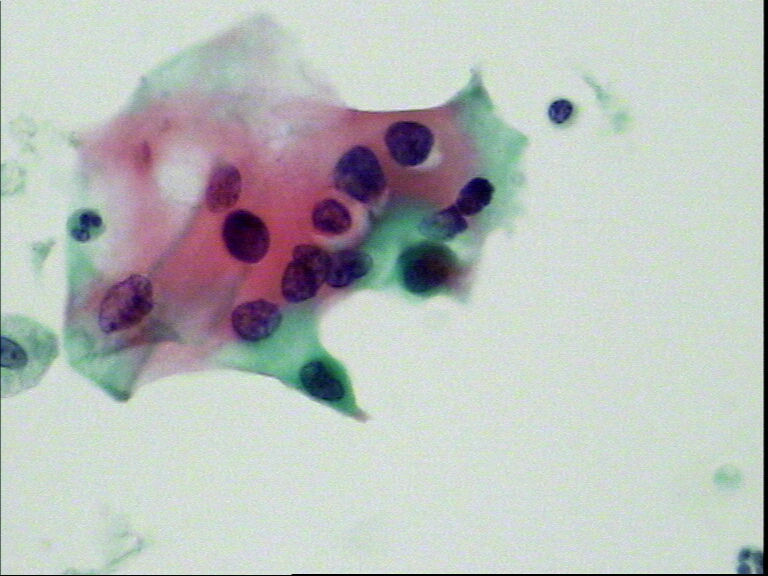

宫颈液基,老年妇女,78岁,临床:宫颈肥大

• 宫颈液基,老年妇女,78岁,临床:宫颈肥大图3

图3

HSIL,建议活检。

HSIL,疑SCC。

HSIL,不除外SCC建议活检。

宫颈高级别上皮内病变,不除外鳞状细胞癌(建议活检)。